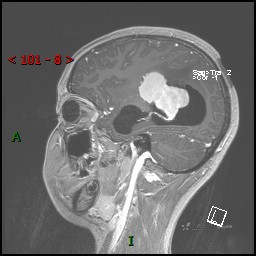

视物模糊发现颅内占位,“豆蔻年华”却承受开颅之痛,所幸一切顺利---结果公布~

患者年龄:14岁

简要病史:患者于1月前无明显诱因出现视物模糊,无明显头痛头晕,无恶心呕吐,无昏迷,无肢体偏瘫等症状,就诊于当地医院头部CT考虑:右侧丘脑、脑室占位。予以对症处置后家属为求进一步诊治来我科,以“颅内占位”收入院。 起病以来,精神、饮食、睡眠欠佳,大小便正常,体力下降,体重无明显变化。

临床诊断:脑室占位

MRI平扫